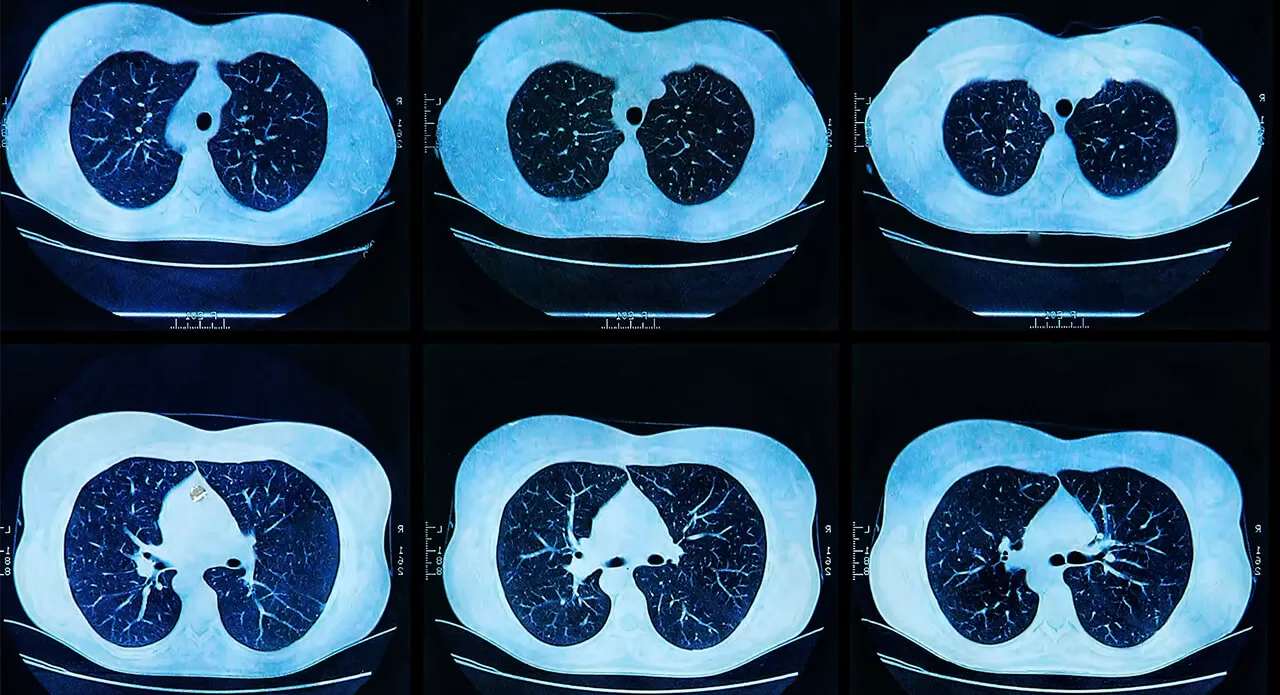

For cancer patients who have been treated with a particular medicine for some time, one of the hurdles many of them face is the tumor developing a resistance to the medicine. It’s a cruel twist that can affect patients being treated for non-small cell lung cancer, which can mutate and begin attacking the brain.

Lung cancer accounts for most cancer-related deaths in the U.S., with non-small cell lung cancer being the most common type,, so the scope of the problem is broad.

But if lung cancer does metastasize into the brain, finding an appropriate cancer-fighting drug can be an immense challenge because of the blood-brain barrier, the thin barrier of tightly packed cells that protects the brain from harmful pathogens and other substances that may disturb the brain’s delicate chemical balance. This barrier is impenetrable to nearly 95 percent of medicines.